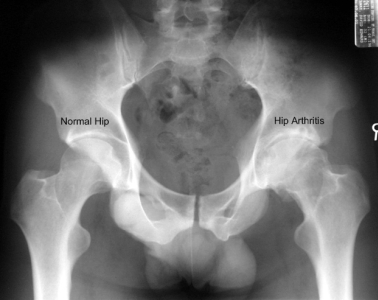

Standing x-rays of the hip joint will give a good assessment of remaining joint space and bone changes related to arthritis:

A simple x-ray should show changes of osteoarthritis. The x-ray findings classically include as joint space narrowing, subarticular sclerosis, osteophytes and degenerative cyst formation.